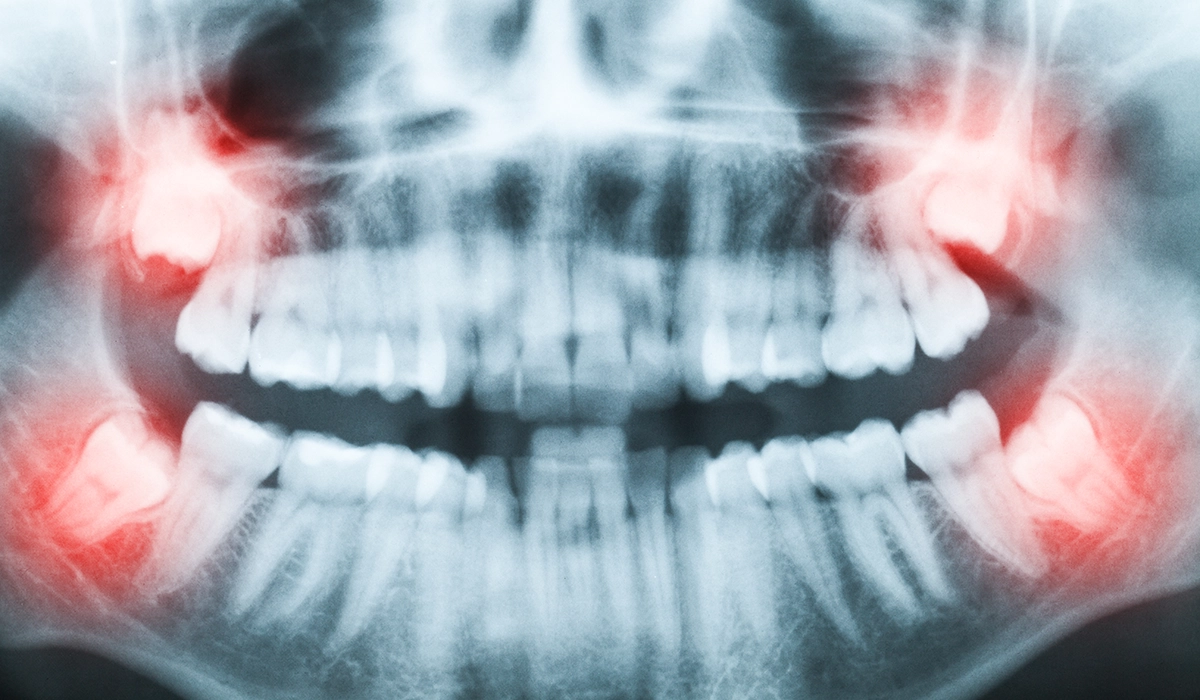

親知らずとは「智歯」や「第3大臼歯」とも呼ばれる歯で、20歳前後で生えてくることが一般的です。親知らずは通常上下左右4本ありますが、全ての親知らずが生えてくるかはわかりません。また、生えてきたとしても斜めに生えてきたり、半分だけ生えたりすることも多いのです。

しかし、今後生えてくる可能性もあり、歯列への影響が全くないとは言い切れません。親知らずがどの状態で歯茎の中に埋まっているかはレントゲンを撮影して確認する必要があります。